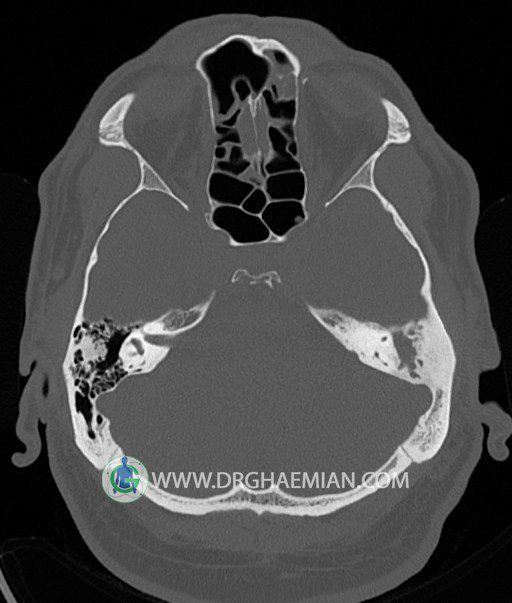

سی تی اسکن گوش داخلی به رادیولوژیست اجازه می دهد تا سطوح مختلف، یا اسلایس هایی از استخوان های که از جمجه به گوش می روند را از طریق امواج ایکس چرخشی مشاهده کند. در این کیس اودیت مدیا، ماستوئیدیت مزمن، اوتیت خارجی، انحراف سپتوم بینی، کونکا بولوزا و افزایش ضخامت سینوس ها مشاهده می شود.

در HRCT از استخوان تمپورال با مقاطع آگزيال ، ساژيتال و کرونال ظريف ( 0.6 mm ) :

– نماي کوکلهآي دو طرف با 2.5 دور گردش مجرا

– نماي cochlear aqueduct

– نماي semicircular canal خلفي ، لترال ، فوقاني و وستيبول

– استخوانچه هاي گوش داخلي شامل malleus ، incus و stapes (دنسيتي و رديف استخوانچه ها )

– نماي oval window و round window ، tympanic cavity ، attic و کانال گوش داخلي

– کانال عصب فاشيال و مسير ان از ناحيه کانال گوش داخلي ، geniculate ganglion تا محل خروج ان از stylomastoid foramen

– نماي tympanic membrane ، کانال ICA ، بولب جوگولار دو طرف

در حد طبيعي است .

– اپاسيتي گوش مياني چپ ناشي از وجود دانسيته نسج نرمي دراطراف استخوانچه ها همراه با اروژن اسکوتوم و

استخوانچه ها بدون جابجايي در رديف استخوانچه ها مشهود است که مطرح کننده اوتيت مديا همراه با نشانه

هاي مشکوک به کولستئاتوم مي باشد .

– اپاسيتي و اسکلروزيس ماستوئيد چپ نشانه ماستوئيديت مزمن

– اپاسيتي کانال گوش خارجي ناشي از دانسيتي نسج نرمي مطرح کننده external otitis

– انحراف سپتوم مياني بيني به راست

– کونکا بولوزا در کونکاي مياني چپ و

– افزايش ضخامت مخاطي در سينوس هاي اتموئيد و ماگزيلاري

اپاسيته